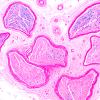

2A6 (Case 2) H&E 20X 10

2A7 (Case 2) H&E 20X 6

2A8 (Case 2) H&E 2X 2

2A9 (Case 2) H&E 10X 5

2A10 (Case 2) H&E 10X 7